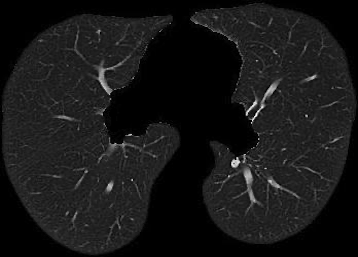

Figure 3 illustrates this further. It presents three cases of unsegmented slices of a CT scan (left column), along with their cases when they are segmented with conventional approaches (middle column) and with our proposed framework SAM2CLIP2SAM (right column). It is evident that the segmentation result with our approach is more accurate and error-prune. In the first case (top row), the mediastinal mass between the left and right lungs is kept when the slices are segmented with conventional approaches, whereas it is not kept (i.e., it is black) when the slices are segmented with our SAM2CLIP2SAM framework. In all cases, one can also note that a bit of the pleural space (e.g. on the peripheral of the lungs) is also kept and is not masked when the slices are segmented with conventional approaches; this is not the case when the slices are segmented with our SAM2CLIP2SAM framework.

Original-Unsegmented Conventionally segmented SAM2CLIP2SAM segmented